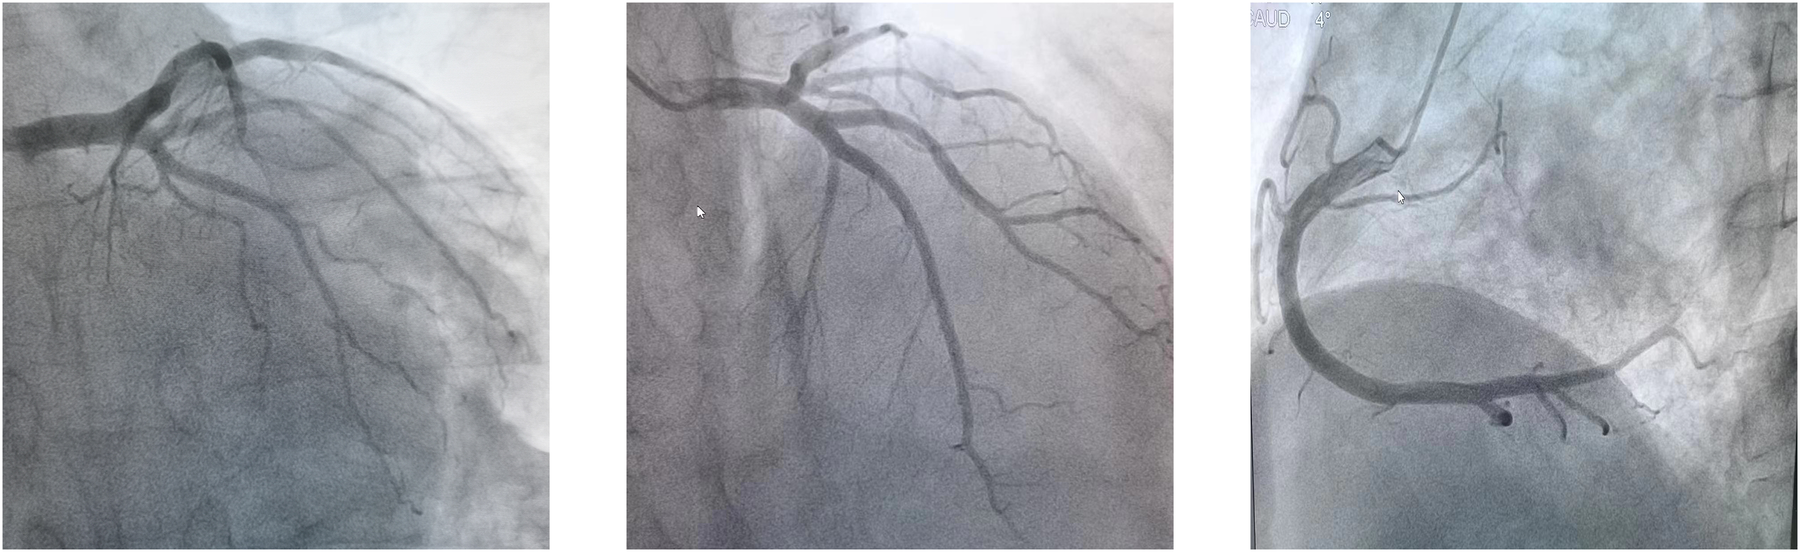

The patient's consciousness was restored (Glasgow Coma score of 13), and sinus rhythm resumed on day 3 of ECMO support. As hemodynamics improved, we gradually discontinued vasoactive medications, leading to the patient's mean arterial pressure surpassing 65 mmHg, LV ejection fraction (LVEF) recovering from 30% to 56%, and lactate levels dropping from over 20 mmol/L to normal (Table 1). Consequently, we have gradually decreased both the ECMO flow rate and the IABP assist ratio. By day 6 of ECMO support, the patient started weaning from ECMO and mechanical ventilation; by day 7, IABP support was successfully terminated. A coronary angiography was subsequently performed, which showed no coronary artery abnormalities (Figure 1). On day 6, levosimendan (0.1 μg/kg/min) was administered to further augment left heart function upon the removal of VA ECMO. On day 12, the patient was transferred from the ICU to the cardiology department, and on day 13, he was discharged. Prior to discharge, echocardiography revealed significant improvement in LV systolic function, with an LVEF of 67% (Figure 2). Notably, the patient did not experience any ECMO-related complications throughout the entire ECMO-assisted treatment. Over the 3-month follow-up period, the patient's urine output and renal function gradually normalized post-discharge, culminating in a successful recovery without any complications. Subsequently, the patient returned to work (Figure 3).

Figure 1

Normal function of coronary artery on coronary arteriography.

In this case, we diagnosed him with FM, based on the symptoms of upper respiratory infection, rapid onset of circulatory failure, electrocardiographic changes, echocardiography, blood test results suggesting elevated troponin levels, and coronary artery disease was ruled out by coronary artery angiography. Our case illustrates the safe application of ECMO in patients experiencing refractory CA due to FM. To our knowledge, this constitutes a rare occurrence of an adult patient with acute FM and CA undergoing sustained CCPR for 120 min and subsequently achieving complete recovery following VA ECMO support without neurological complications. It is widely accepted that a short duration of CPR correlates with a favorable neurological outcome (14). Consequently, it is recommended that ECPR be initiated within 40 min and no later than 60 min post-onset of CA, as suggested by the Extracorporeal Life Support Organization (15). Beyond the 40-minute threshold, the survival rate with a favorable neurological prognosis significantly decreases from over 30% to approximately 15% (16, 17). Upon initiation of ECPR, extracorporeal circulation ensures perfusion to systemic organs, even in the absence of autonomic circulation. This results in enhanced coronary perfusion pressure, ROSC, and successful defibrillation compared to CCPR (18, 19).